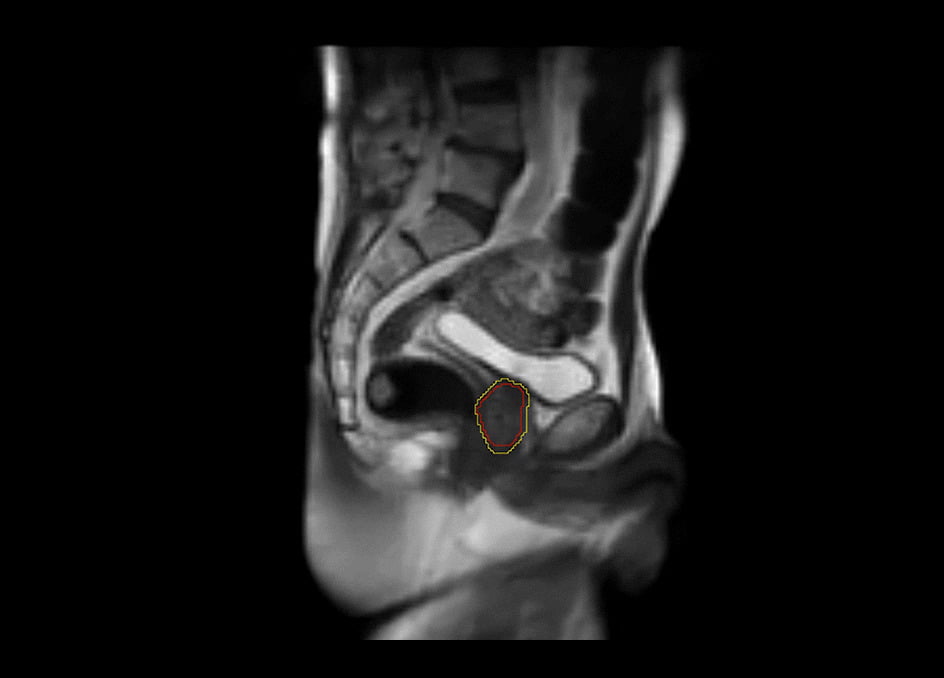

軟部組織の描出を得意とするMRIと放射線治療装置を組み合わせたMRリニアックシステム。放射線治療における次世代のソリューション。

MRIdianシステムを使用することによって、軟部組織を観察し、照射を視覚化して調整し、治療をコントロールすることが可能です。